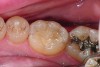

Fig 6. In Case 2, pretreatment view of multiple non-carious cervical lesions.